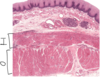

Rectum -

rectum is the terminal portion of the sigmoid colon, and therefore, it is similar in structure to the colon. At the macroscopic level, this area has longitudinal folds called rectal columns. The mucosa contains numerous goblet cells, and the submucosa may have hemorrhoidal venous plexuses which can extend into the lamina propria. The mascularis externa has

both inner circular and outer longitudinal smooth muscle layers. Arrows: some of the blood channels.